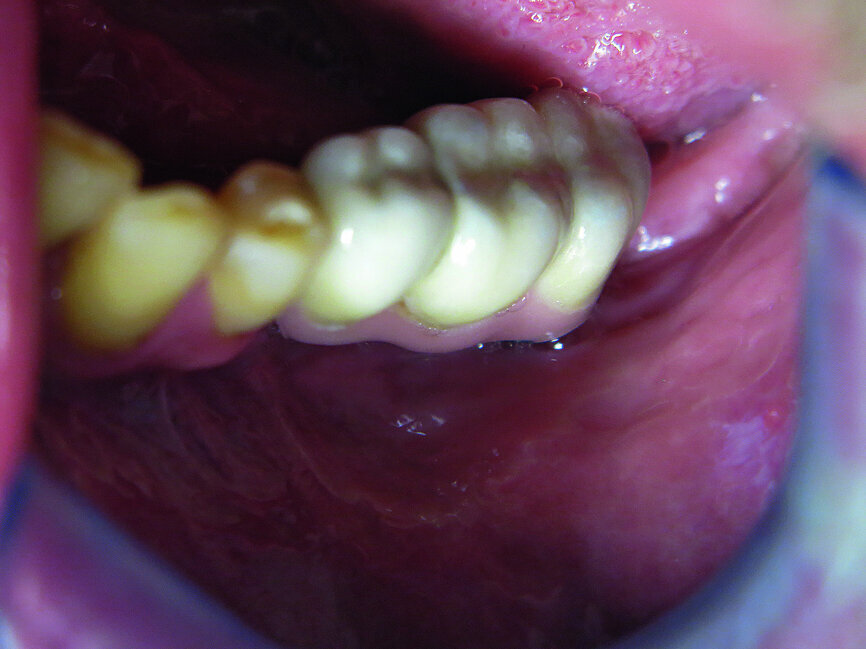

Fig. 21: Final situation.

The first was a 51-year-old patient who smoked 30 cigarettes per day and suffered from diabetes and stress (Figs. 1–8). The second was a 76-year-old male patient in good physical condition who smoked 40 cigarettes per day. He underwent reconstruction of the premaxilla (Figs. 9–13). The third was a healthy female patient of 24 years of age who smoked 20 cigarettes per day. She required a sinus lift in region #25 (Figs. 14–21). The patients were informed of the intended process in detail and signed the surgical protocol containing information concerning possible risks of failure and complications, as well as information on the alloplastic and synthetic materials to be used.

In two cases, a thickness flap was raised after 12 weeks in order to access the cover screw. In 85 % of cases implant stability was evaluated using resonance frequency analysis (Osstell ISQ). A healing abutment was placed and the flap was sutured using 4/0 sutures (RESORBA Medical). Finally, after nearly two weeks, a titanium abutment was placed and a cemented metal-ceramic restoration was fabricated.